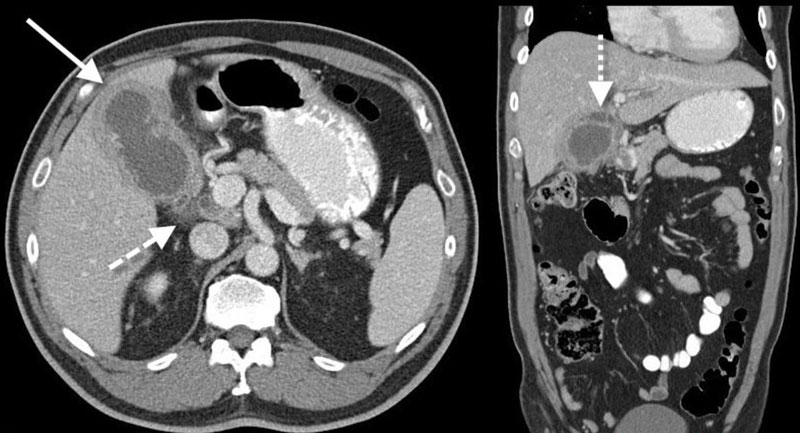

Что МРТ желчного пузыря показывает

В клинической практике чаще всего назначается МР-обследование гепатобилиарной системы для выявления холециститов, холангитов – воспалительных процессов внутри желчного пузыря, вне- и внутрипеченочных протоков. Состояние возникает у пациентов с желчнокаменной болезнью, приводящей к острому болевому синдрому в правом подреберье.

Исследование рекомендуется для оценки динамики восстановления ткани после удаления желчного пузыря, контроля эффективности лечения холангитов, холедохолитиаза (камней).

При отсутствии клиники поражения печени МР-сканирование назначается для выявления сужений трубчатых структур, деформаций желчных путей.

Доскональное изучение протоков и пузыря необходимо при желчнокаменной болезни. При патологии образуются кристаллизованные соли твердой структуры, затрудняющие физиологическое движение желчи. Диагностика болезни на ранней стадии предотвращает не только боль в правом подреберье, но и необходимость оперативного удаления холедоха при закупорке проходимости по протокам.

Нарушение попадания желчи в двенадцатиперстную кишку сопровождается расстройством переваривания жиров, горечью во рту, рвотой и тошнотой. Для выявления конкрементов в желчном пузыре не рационально делать МР-сканирование. Нозологию хорошо диагностирует УЗИ. Магнитно-резонансное обследование проводится для верификации закупорки внутрипеченочных желчных протоков при гепатитах, гепатозах.

Клинику желчнокаменной болезни симулируют полипы желчного пузыря – патологические разрастания эпителия. Рост образования внутрь полости затрудняет желчевыделение. Полипозные образования прослеживаются на УЗИ, но с помощью исследования нельзя определить точные размеры и структуру нароста.